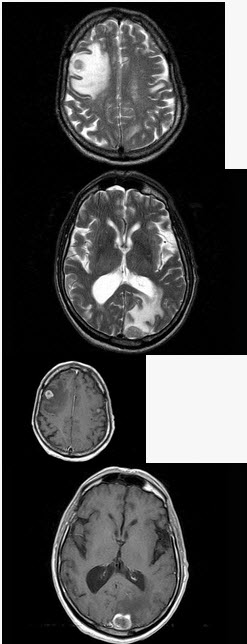

男,77岁,胃癌术后2年,头痛1个月,结合图像,最可能的诊断是()

A . 脑脓肿

B . 松果体瘤

C . 神经胶质瘤

D . 胃癌脑转移

E . 脑膜炎

男,77岁,胃癌术后2年,头痛1月,请结合影像图像选择最可能的诊断()

[单选题]男,77岁,胃癌术后2年,头痛1月,请结合影像图像选择最可能的诊断()A . 脑脓肿B . 松果体瘤C . 神经胶质瘤D . 胃癌脑转移E . 脑膜炎

男,77岁,胃癌术后2年,头痛1月,请结合影像图像选择最可能的诊断 ( )<img style="width: 226px; height: 259px;" src=&quo

[单选题]男,77岁,胃癌术后2年,头痛1月,请结合影像图像选择最可能的诊断 ( )A.脑脓肿B.松果体瘤C.神经胶质瘤D.胃癌脑转移E.脑膜炎